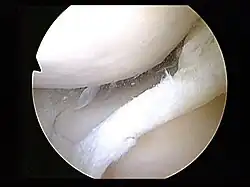

Arthroscopy is a surgical technique in which a joint is operated on using an endoscopic camera as opposed to open surgery on the joint. The meniscus can either be repaired or completely removed.[20] Surgery is not appropriate for a degenerative meniscus tear, absent locking or catching of the knee, recurrent effusion or persistent pain.[25] Evidence suggests that it is no better than conservative management in those with and without osteoarthritis.[31][32] Surgery appears to offer no benefit to adults who have mild arthritis.[32]